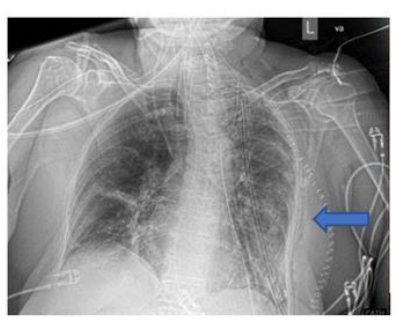

A 74-year.old woman with a past medical history significant for essential hypertension, former smoker, and goiter presented to the urgency room with dyspnea on exertion of one month of evolution, 'Ihe patient has no known asbestos exposure. Physical examination was remarkable for decreased breath sounds on the left hemithorax, Chest Xray was initially evaluated and showed evidence of near complete opacification of the left lung, Given this finding, a chest CT scan was performed which revealed a 15.1 cm x II cm x 19.3 cm extrapulmonary and intrapulmonary mass in the left hemithorax with compression and subtotal collapse of the left lower lung, A PET CT scan was also performed and showed a 13 cm FDG avid mass in the left chest involving nearly all the left lower lung, and the posterior segment of the left upper lung. This is a tool which helps to categorizæ the tumor between malignant and benign, depending on the of its metabolic activity

A CT guided core biopsy of the lesion was done, and pathology was consistent with a solitary pleural fibrous tumor. Immunohistxhemistry was strongly positive for CD34, STAT6, and negative for pankeratin. The patient was then referred to a thoracic surgery specialist for evaluation. She was taken to the operating room and underwent a tumor embolization, to reduce blood loss and then a complete tumor resection was perfromed. The surgery was successful with an encouraging prognosis.